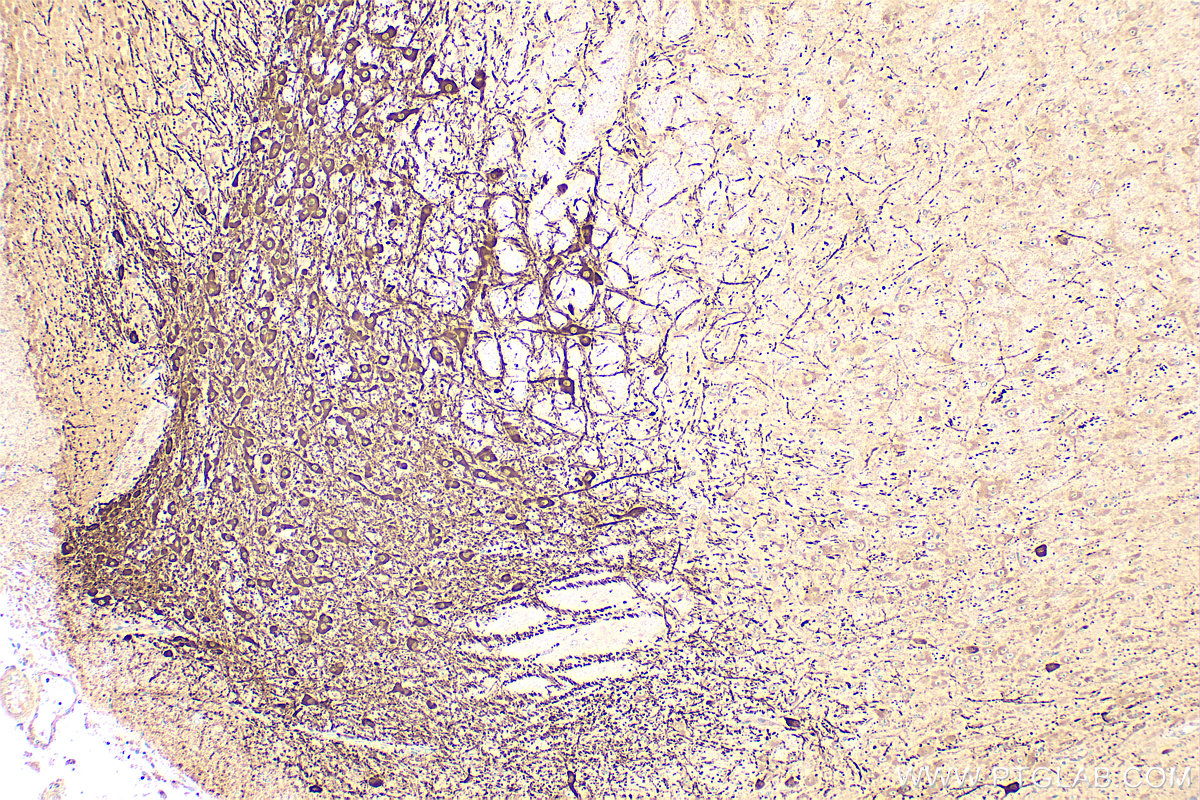

| Positive IHC detected in | mouse brain tissue Note: suggested antigen retrieval with TE buffer pH 9.0; (*) Alternatively, antigen retrieval may be performed with citrate buffer pH 6.0 |

| Immunohistochemistry (IHC) | IHC : 1:500-1:2000 |